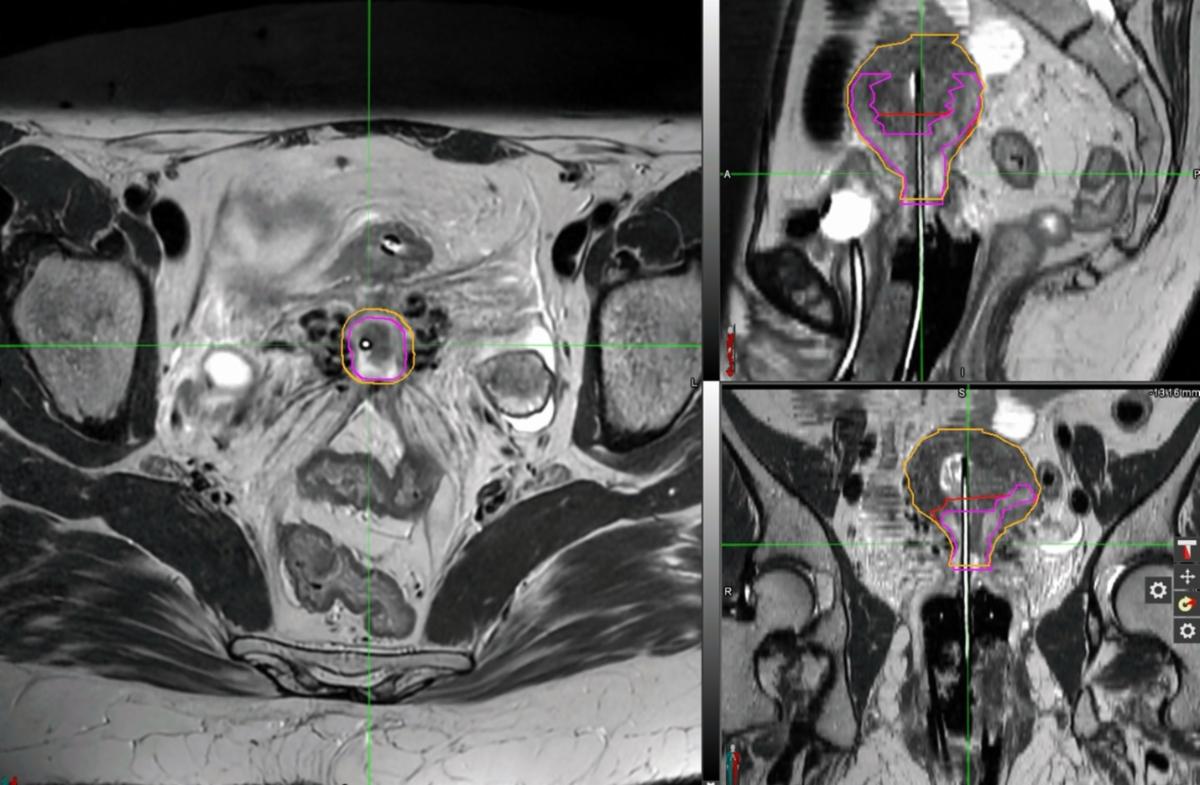

For the second fraction, due to uterine size and myometrial involvement, a 3 cm Rotte-Y applicator was used instead of a uterine tandem. Interstitial needles were omitted to minimize risk of bleeding and tissue damage, and the fact that there was no significant residual parametrial disease. The dual tandems of the Rotte Y applicator were rotated into position, and secured together, confirmed with ultrasound. Similar to fraction #1, 25 mm MRI/CT-compatible ovoids were selected and assembled onto colpostats. The ovoids/colpostats were advanced into the vaginal fornices, and the 2 tandems of the Rotte Y were centered between the ovoids. The colpostats were secured together with a simple bridge. A rectal paddle was placed under the ovoids. Wet Kerlix gauze packing was placed to help displace the bladder and rectum and to secure the applicators. The Rotte Y applicator and the colpostats were secured together with foam tape. Since Rotte-Y applicator is not MRI-compatible, she underwent high-quality CT to be used for planning and reconstruction, and were fused to the MRI from her fraction to assist with GTV and HR-CTV delineation. This plan proved to be dosimetrically superior with improvement in HR-CTV V90% (91.5% to 97.8%), HR-CTV D90 (6.5 to 7.4 Gy, 13.9%), HR-CTV D98 (5.1 Gy to 6.3 Gy, 23.5%). This was also associated with improvement in bladder (-9%), bowel (-10.9%), and rectal (-1.3%) D2cc, though with increase in sigmoid dose given the anatomy that day (+14.4%).

Given optimal dosimetry and target coverage, customized Rotte-Y/ovoids/colpostats applicator set was used for subsequent fractions. Figures 4A-B summarize fraction by fraction change in target coverage and OAR doses, with specific doses listed in Table 1. She tolerated treatments exceptionally well with no apparent procedural complications.

Figure 3B-E: HDR-BT Fraction 1 MRI in MIM treatment-planning software